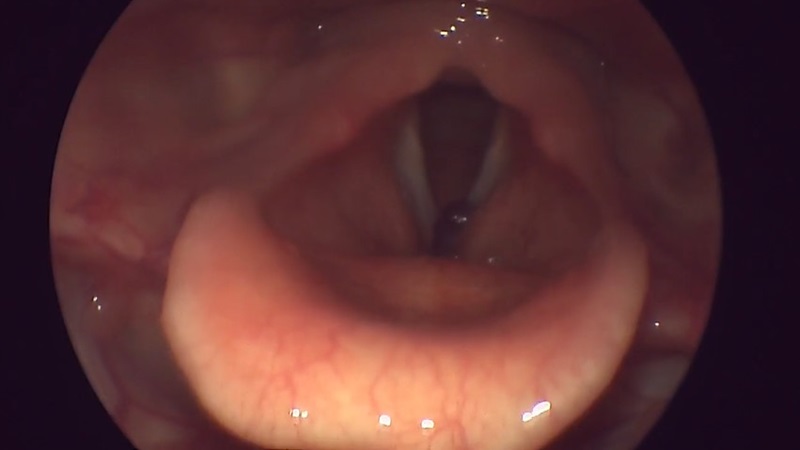

Фото 1: Пацієнтка 18 років звернулася зі скаргами на осиплість за активної розмови, відчуттям стороннього предмету в глотці. Ці скарги виникли після перенесеного ларинготрахеїту п'ять місяців тому. Курс консервативного лікування без ефекту. При проведенні ендоскопії глотки – у передньому полюсі лівої голосової складки новоутворення багряного кольору овальної форми з ковткою поверхнею. Тривалість операції від 20 до 40 хвилин.

Фото 2: Пацієнтка 44 роки. Звернулася зі скаргами на осиплість протягом останніх місяців. Курить. Під час проведення відеоендоскопії гортані-голосові складки стовщені, склоподібні, моторика при фонації збережена. Тривалість операції до 40 хвилин.